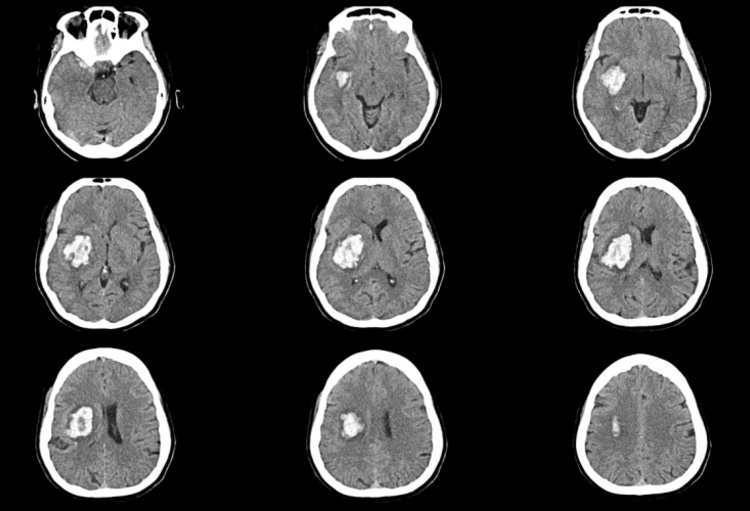

La place de la chirurgie mini-invasive dans l’hémorragie intracérébrale spontanée: étude MIND

L’hémorragie intracérébrale spontanée (HIC-S) représente environ 10 à 15% des AVC et demeure l’une des formes d’AVC les plus sévères, avec une mortalité à court terme estimée entre 30 et 40% et un taux élevé de handicap fonctionnel chez les survivants. Malgré des décennies de...